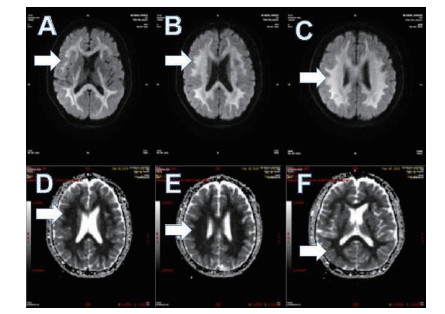

2 结果 2.1 基本资料及头颅核磁特征本观察研究最终纳入患者51例,中毒患者的头颅核磁特征表现为:在MRI的常规序列(T1\T2\FLAIR)病灶显示不明显,但在DWI表现为高信号,ADC值下降呈低信号。病变部位主要是胼胝体的压部(所有阳性病例胼胝体压部均受损),病变也可以形成以胼胝体为中心的广泛白质病变,皮质不受损害。见图 1,2。

| 图 1 A.T1序列/B.T2序列/C.FLAIR序列均无异常;D.DWI系列上为高信号(箭头所示) |

| 图 2 A\C弥散像呈高信号,B\D ADC图呈低信号(箭头所示) |